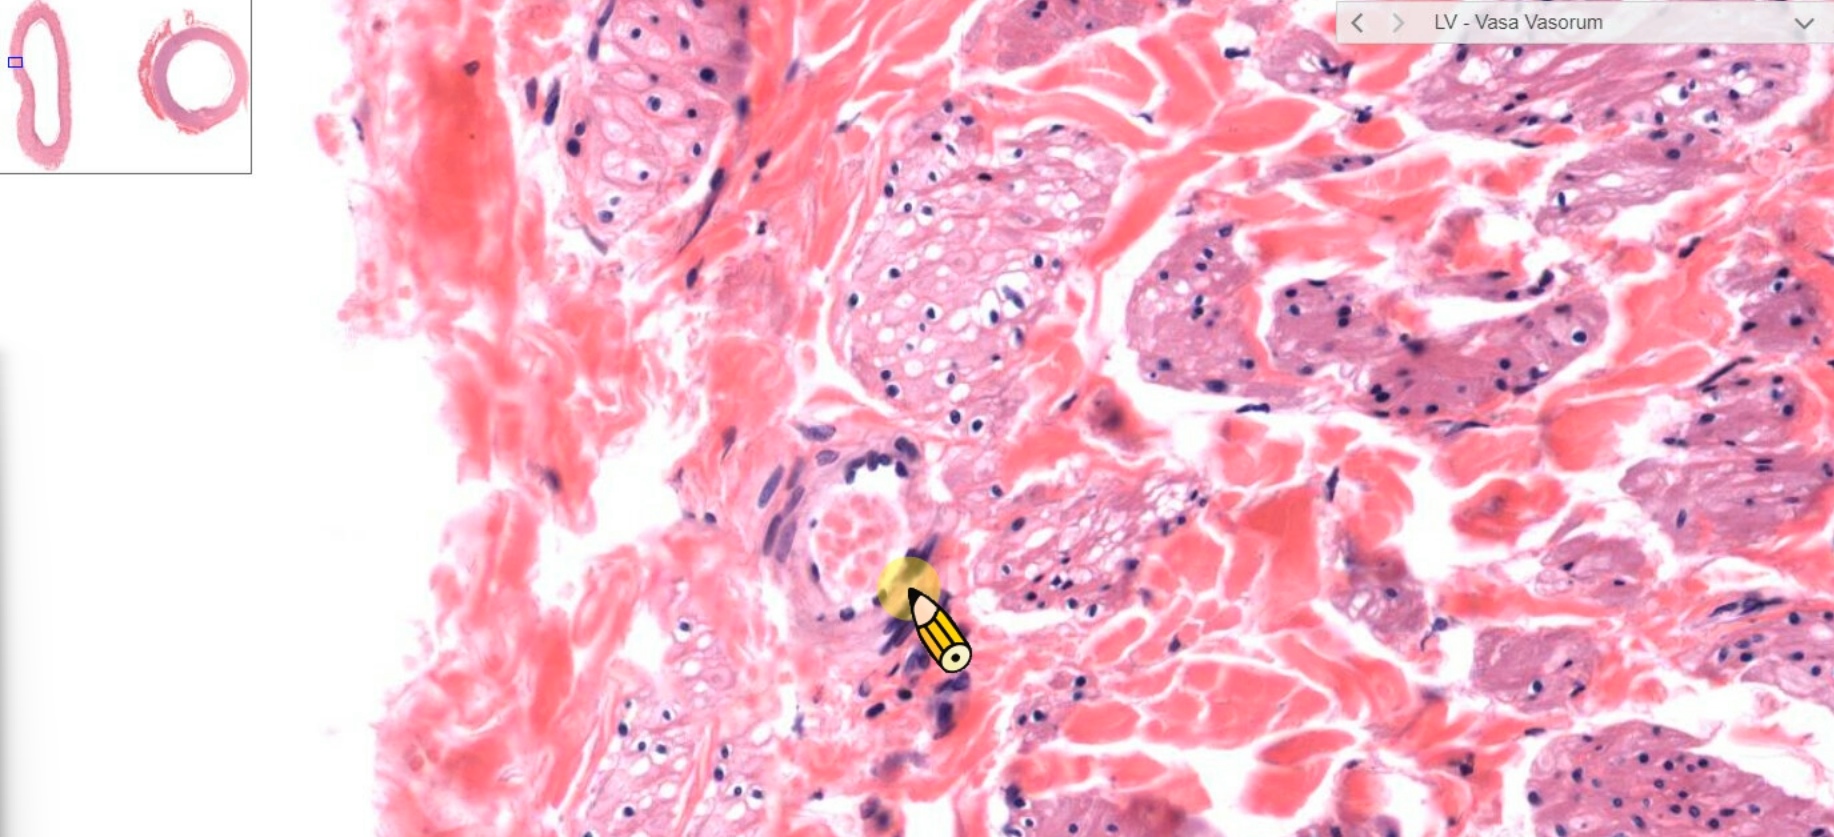

- vasa vasorum(血管滋養管)

vasa vasorum |

vasa vasorum